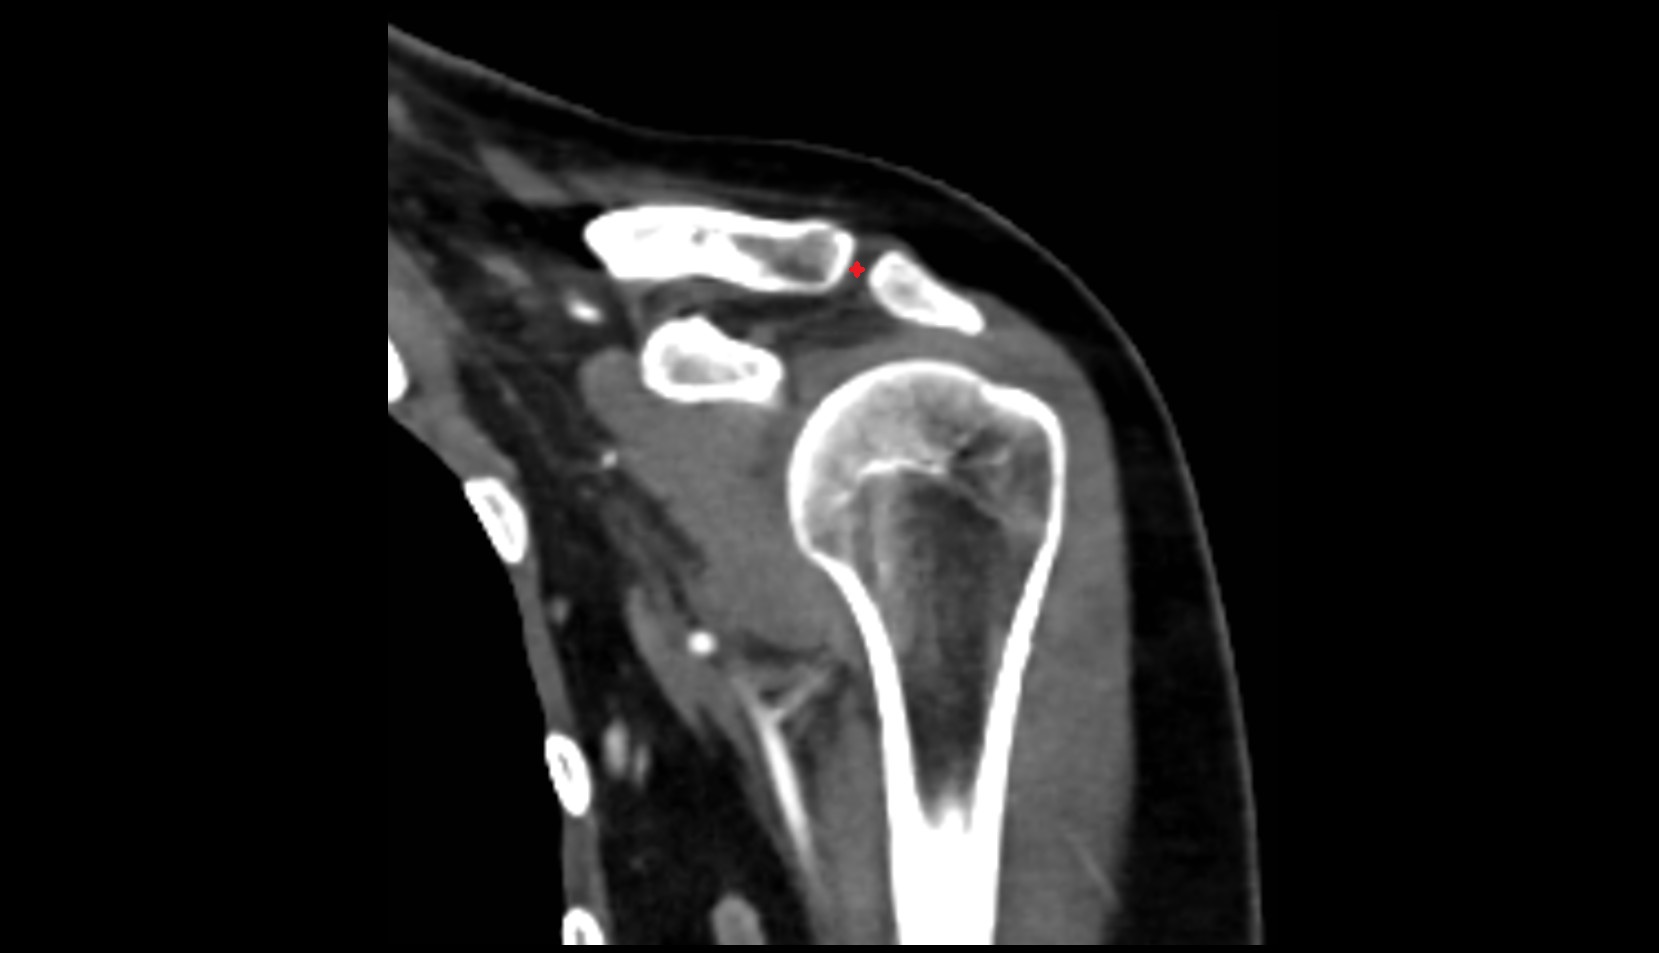

- Shoulder joint (glenohumeral joint)

- Acromioclavicular joint